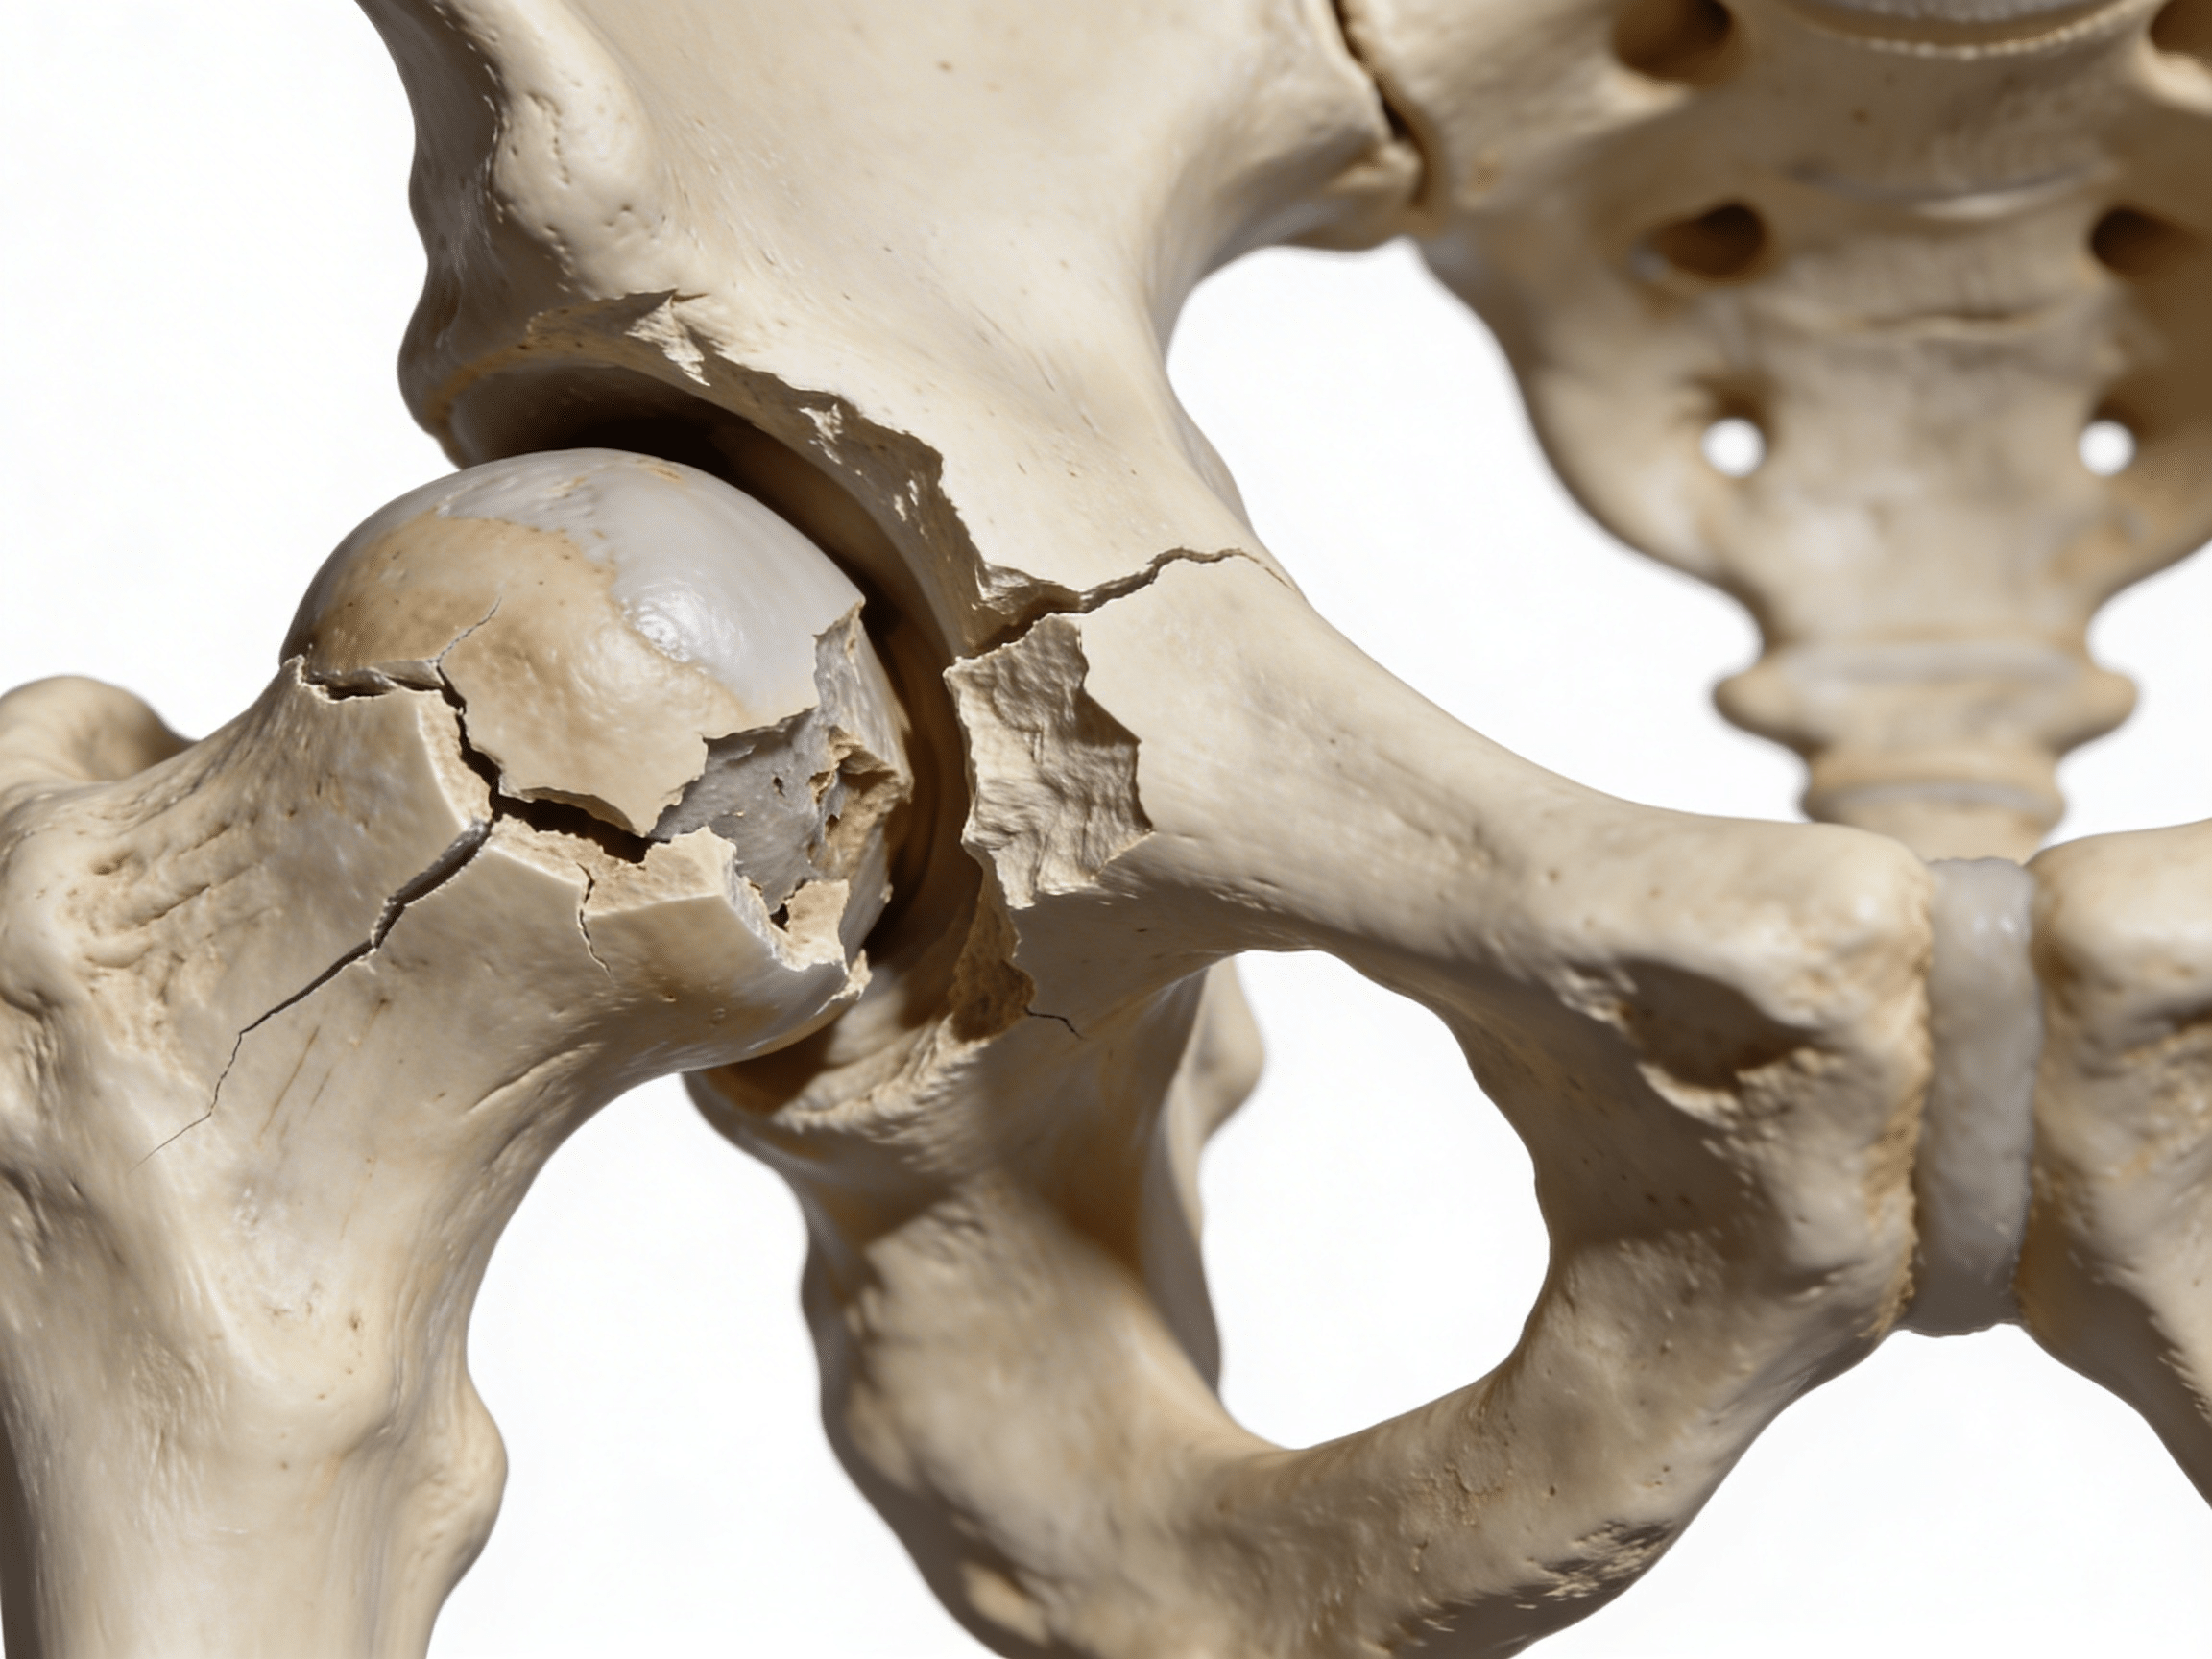

Research from the Journal of Bone and Joint Surgery demonstrates that delayed hip fracture surgery increases 30-day mortality rates by 41% when operative treatment exceeds 24 hours, with each additional 12-hour delay associated with increased complications including pneumonia, pressure ulcers, and venous thromboembolism[7]. This timeline becomes even more critical for displaced femoral neck fractures, where avascular necrosis rates increase from 15% to 35% when surgical fixation exceeds 6 hours, with immediate reduction within 6 hours preventing devastating osteonecrosis requiring total hip replacement[8]. Our orthopedic emergency capabilities include immediate Buck's traction application, pain management protocols, and urgent surgical coordination when hip fractures require operative fixation preventing complications that conservative delay causes.

Priority ER's diagnostic capabilities for pelvic and hip fractures exceed Joint Commission standards for emergency departments[14], featuring advanced digital radiography systems plus CT scanning with IV contrast providing immediate identification of femoral neck fractures, intertrochanteric fractures, and pelvic ring disruptions requiring emergency surgical intervention. Our emergency physicians trained in Garden classification (Types I-IV for femoral neck fractures based on displacement and alignment), AO/OTA classification for complex fractures, and Young-Burgess classification for pelvic ring injuries ensure accurate assessment guiding life-saving treatment decisions[15]. The integration of massive transfusion protocols, pelvic binder application, and Buck's traction stabilization prevents complications that delayed treatment causes including hemorrhagic shock, fat embolism, and avascular necrosis.

What's the difference between femoral neck and intertrochanteric hip fractures?

Femoral neck fractures occur within the hip joint capsule, carrying high avascular necrosis risk (15-35%) requiring urgent surgery within 6-12 hours when displaced. Intertrochanteric fractures occur outside the joint capsule between the greater and lesser trochanters, having better blood supply with lower AVN risk but often requiring more extensive surgical fixation. Priority ER emergency physicians use Garden classification for femoral neck fractures and AO/OTA classification for intertrochanteric fractures, determining urgency and coordinating appropriate surgical approach ensuring optimal outcomes.